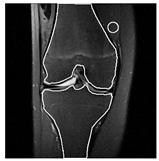

| Patient | Patient ID | Image Label | Image Prediction | Original Image | High Intensity Masking Image |

|---|---|---|---|---|---|

| Non-edema | 2 | Non-edema | Edema | ![]() | ![]() |

| Non-edema | 5 | Non-edema | Edema | ![]() | ![]() |

| Non-edema | 20 | Non-edema | Edema | ![]() | ![]() |

| Non-edema | 30 | Non-edema | Edema | ![]() | ![]() |